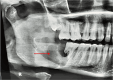

Granular Cell Ameloblastomatous Transformation From the Remnants of a Dentigerous Cyst: A Unique Case Report

Granular cell ameloblastoma is a unique, infrequent histologic variant of unicystic/multicystic ameloblastoma showing distinct histologic and immunohistochemical features. The prognosis and treatment are similar to other common subtypes of solid or multicystic ameloblastoma. Granular cell ameloblastoma should be distinguished from other lesions with granular cells mainly due to its high risk of recurrence. Although it is rare, it has greater recurrence potential and chances of malignant potential. A better knowledge of the molecular pathogenesis of ameloblastoma and its various subtypes may provide diagnostic and therapeutic benefits. We are reporting a case of granular cell ameloblastoma arising from the wall of a dentigerous cyst. The lining of the dentigerous cyst shows a potential for neoplastic transformation to ameloblastoma, squamous cell carcinoma, and mucoepidermoid carcinoma.